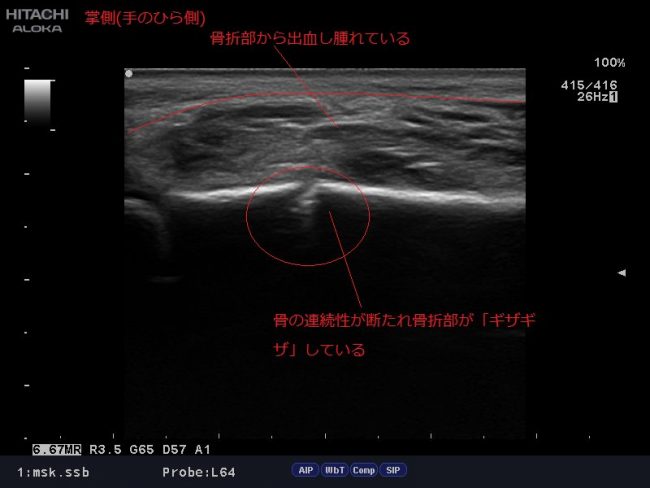

エコーとは人間の耳では聴こえない高い周波数の音波(超音波)を体表からプローブを介して発射し、体内の硬い組織(骨や臓器)で反射して戻ってきた音波を画像化する装置です。胎内の赤ちゃんの様子をみたり、健康診断で内臓を観察する際に用いられることが一般的ですが、骨折の有無や筋肉組織の状態(肉ばなれ)、靭帯損傷・関節部分の骨の変形、軟骨の摩耗具合等の評価にも用いられます。

当院では、このエコーを使用し患部の状態を観察する事で評価・治療効果の増大を図っています。